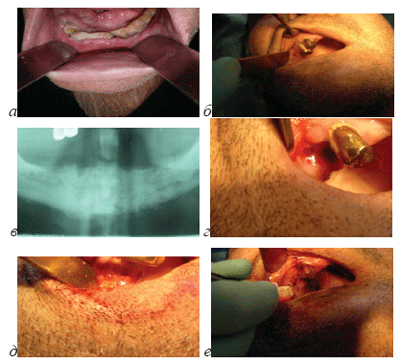

Больной Г. 53 года, мужского пола, обратился с жа-лобой на постоянную боль в области зуба 14. В анамнезе отмечает употребление наркотика “крокодил” (дезоморфин) в течение 18 месяцев. Последний раз употреблял 20 дней назад до операции. 10 дней назад оперировался по поводу остеонекроза нижней челюсти (рис.5а).

Объективно на зубе 14 присутствует искусственная металлическая коронка. У зуба 14 отмечается подвижность 2-ой степени. Слизистая оболочка имеет бледно-розовую окраску. В области зубов 13,14 наблюдаются зубные отложения. Перкуссия зуба резко болезненная. Наблюдается гноетечение из зубодесневого кармана. Рентгенологически (до операции по поводу остеонекроза нижней челюсти, кроме признаков остеонекроза, наблюдается

Рис. 5. Больной Г. с остеонекрозом нижней челюсти, применяющий наркотик “крокодил” (дезоморфин), а)область остеонекроза нижней челюсти до операции, б) область зубов 13,14, в) ортопантомограмма-видны резорбция краев лунки зуба 14 больше 1/2 ее высоты, расширение периодонтальной щели зуба 14, г) рана после удаления зуба 14, д) рана после резекции лунки зуба 14, е) рана после закрытия узловыми швами.

резорбция краев лунки зуба 14 больше 1/2 ее высоты, расширение периодонтальной щели зуба 14 (рис.5в).

Диагноз: обострение хронического периодонтита, хронический пародонтит.

Произведена операция удаления зуба 14 по 2-ому варианту. Под местным обезболиванием удален зуб 14 (рис.5г), образован слизисто-надкостничный лоскут, оголена подлежащая кость. Так как была обнаружена резорбция краев лунки зуба 14 до 1/2 ее высоты, то про-ведена полная резекция лунки зуба (рис.5д). После укорочения межзубной перегородки и мобилизации слизистонадкостничного лоскута, рана закрылась наглухо узловыми швами (рис.5е). Рана заживала первичным натяжением, без осложнений. Швы были удалены на 10 день после операции. Через 2 месяца после удаления, на месте операции слизистая оболочка имела нормальную розовую окраску, обнаруживался тонкий рубец и дефект костной ткани альвеолярного отростка. Больной никаких жалоб не предъявлял.